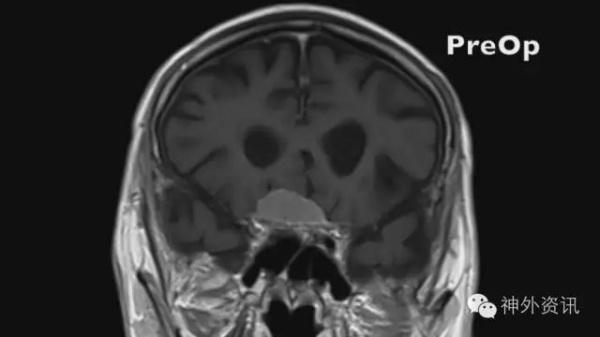

图11、12是一例常见的基底位于鞍结节鞍隔脑膜瘤。手术常规右侧LSO入路,先断肿瘤基底,然后分水离肿瘤界面,予以切除。

图11. 鞍结节鞍隔脑膜瘤。

图12. 鞍结节鞍隔脑膜瘤

图13. 术中探查右侧第二间隙。

图14. 右侧颈内动脉撕裂,动脉血满视野。

术中在探查右侧第二间隙时,较尖的双极头端不慎将颈内动脉撕破,动脉血汹涌(图13、图14);此种情况下,压迫止血肯定不靠谱,予以9-0缝合亦不现实,因此Sundt Clip Graft可能是唯一救命方案。选用5mm内径的Sundt Clip Graft,上夹固定后,止血彻底;术中超声探查血流通畅;继续切除肿瘤完成手术,术后复查良好。

图15. Sundt Clip Graft包裹颈内动脉破口。

图16. 术后复查见脑组织无肿胀缺血。